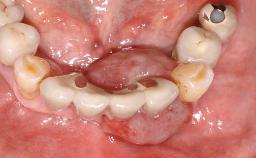

Surgical treatment of a 68-year-old female patient with a distal extension situation in the left mandible. As the CBCT analysis reveals, the bone crest anatomy in the area is not ideal and necessitates an augmentation procedure to achieve a good long-term prognosis for the planned implants and their prostheses.